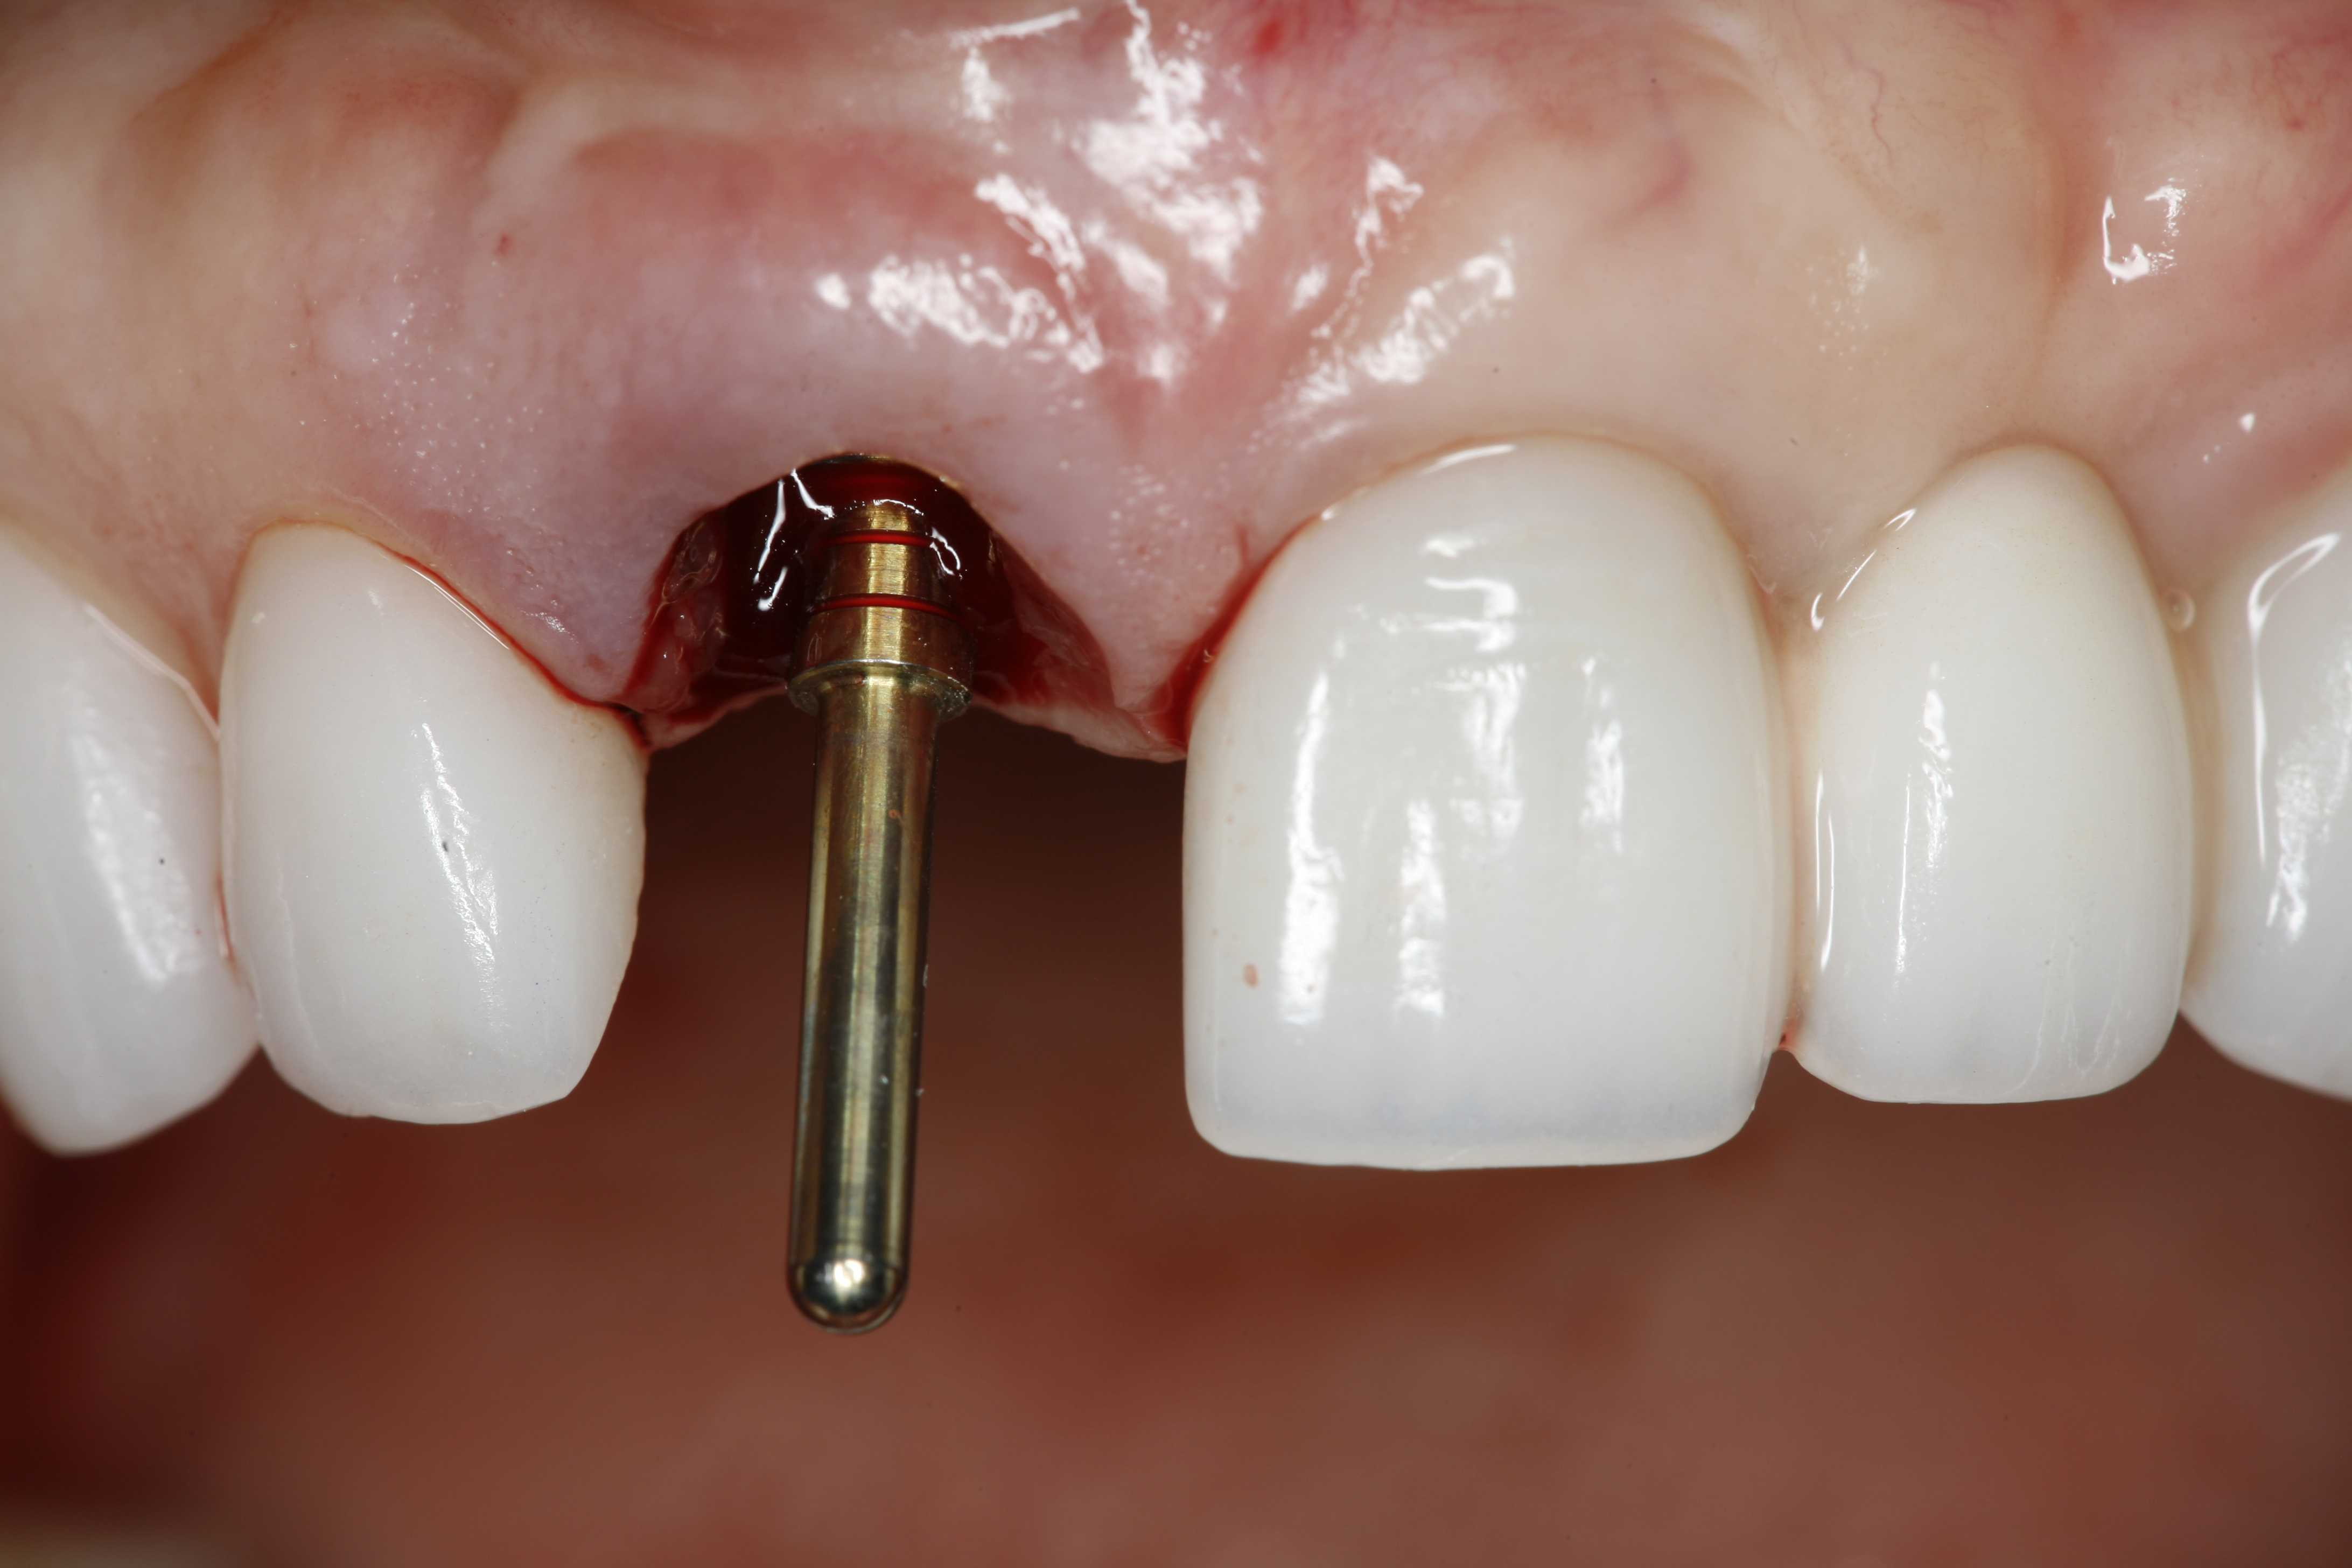

An osteotomy that used the dense cortical bone on the palatal aspect of the extraction socket was prepared, and a guide pin was inserted (Figure 5) to verify that the angulation was ideal. The implant was then inserted (Figure 6). Figure 7 shows the occlusal view of the implant in position. Note the gap between the palatally oriented implant and the buccal plate of the extraction socket.

Fig 5. A guide pin was used to check the angulation and depth of the prepared osteotomy.

Figure 5

Fig 6. Implant insertion.

Figure 6